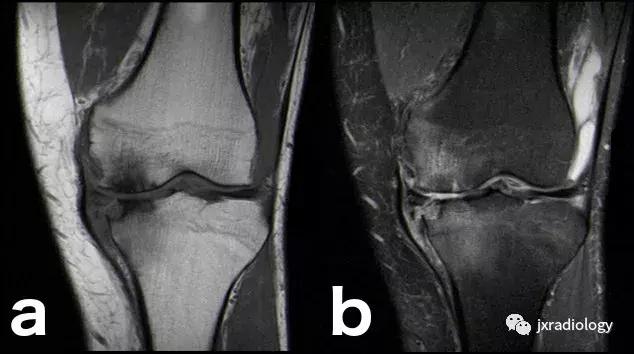

图21:这名患者的炎症性关节炎表现为围绕内侧股 - 胫室侵蚀性改变的骨髓水肿。它是血管源性骨髓水肿的一个例子(继发于血液和血清传递至骨髓空间毛细血管床)(a,b:冠状T1-WI和PD-FS-WI)。